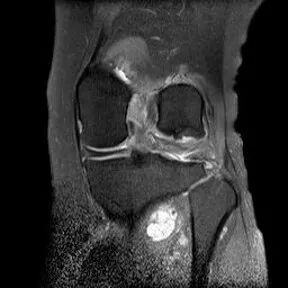

半月板撕裂:桶柄状撕裂(双前角征)